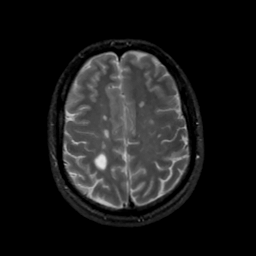

MR Study #13, May 19, 1991 -- Slice #37